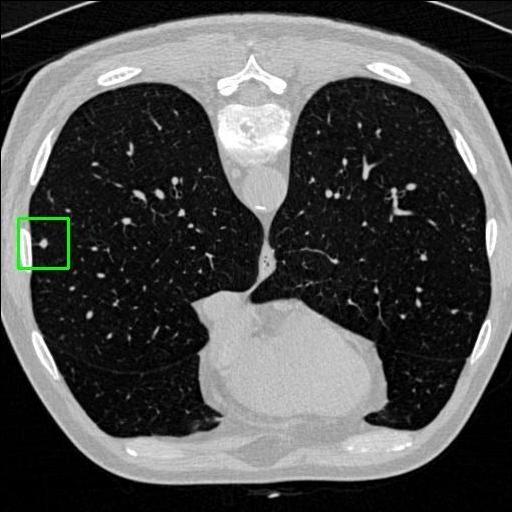

We developed an AI-based system using deep learning models for analyzing lung CT scans to detect and classify pulmonary nodules. We chose the YOLOv11 architecture for its enhanced object detection capability and adapted it specifically for medical imaging, incorporating pixel-level precision and severity classification.

Classification into three severity levels with colored bounding boxes.

Maintaining performance on small, complex features like micro-nodules tested the limits of traditional object detectors.

Designed a severity classification system that categorizes nodules into null, moderate, and severe using colored bounding boxes, assisting in rapid clinical decision-making.